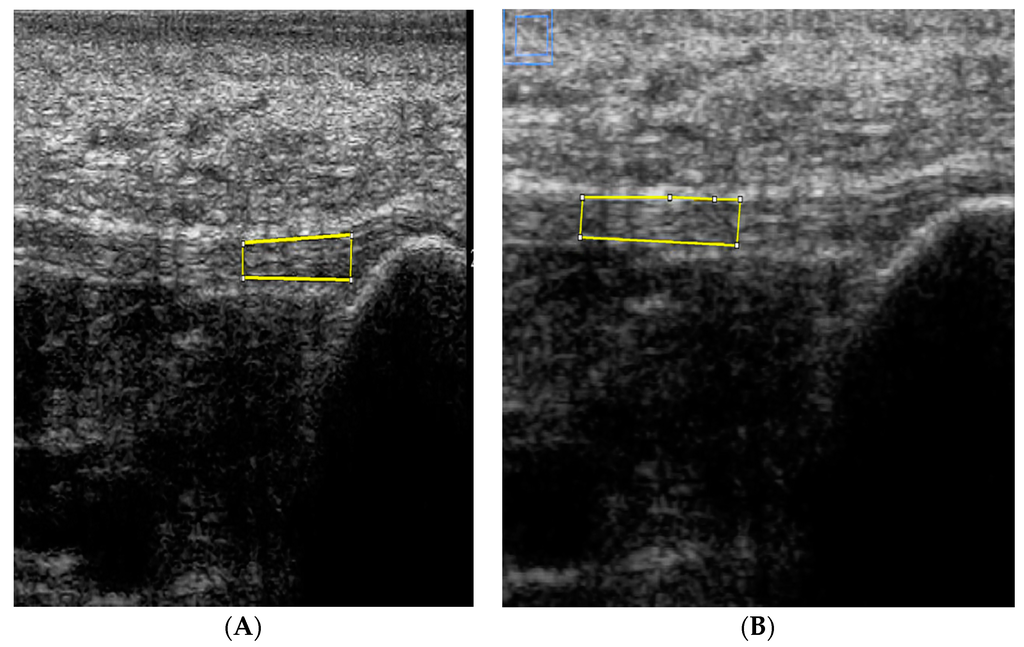

2.2. Test Procedure

2.3. Image Analysis